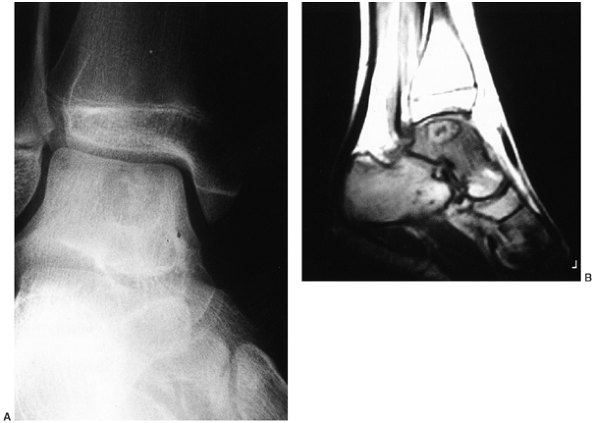

Figure 14.4 A:

Plain radiograph, lateral view, of an 18-year-old woman’s ankle. She complained of severe pain for 6 months, which was totally relieved by aspirin. There is a small erosion in the anterior neck of her talus. (Her computed tomography scan is seen in Fig. 14.3.) B: The sagittal view of a T1-weighted magnetic resonance image shows the lesion in her anterior talus. C: The T2-weighted magnetic resonance image reveals the extensive edema that is characteristic of osteoid osteoma. |

them are found in the femur or the tibia. The other half are

distributed throughout the rest of the skeleton (Fig. 14.4). The proximal femur is a common site. It is also